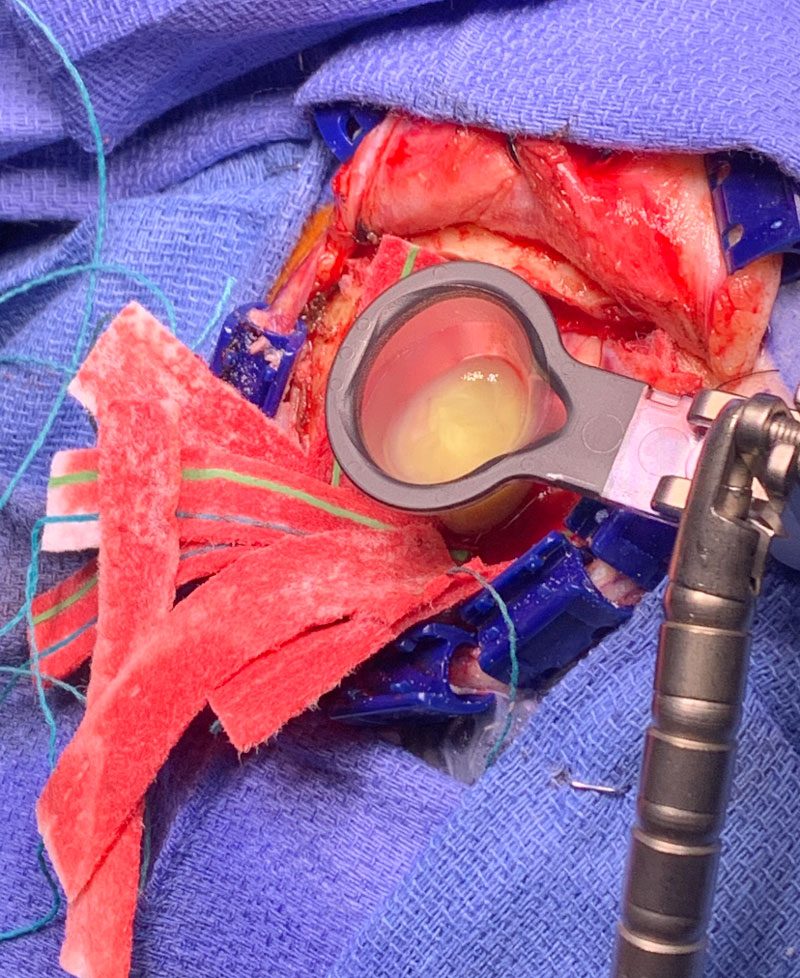

Because the lesion was sizeable, and causing much mass effect, and the diagnosis was unclear, and the patient was young with no other existing disease, it was decided to emergently bring the patient to the operating room for surgical removal of the mass. Surgery was performed by Dr. Michael Brisman. Stereotactic Brainlab navigation was utilized. A small left frontal craniotomy was performed. After making a small cortical incision, the Vycor transparent tubular retractor was inserted into the lesion. Thick yellow liquid was encountered under pressure consistent with frank purulence. (Image 2 shows intra-operative image of Vycor tubular retractor in deep left frontal mass with thick purulent material coming out under pressure.) Cultures were sent. The pus was fully washed out with gentle antibiotic irrigation.

Image 2: Intra-operative image of Vycor tubular retractor in deep left frontal mass with thick purulent material coming out under pressure.